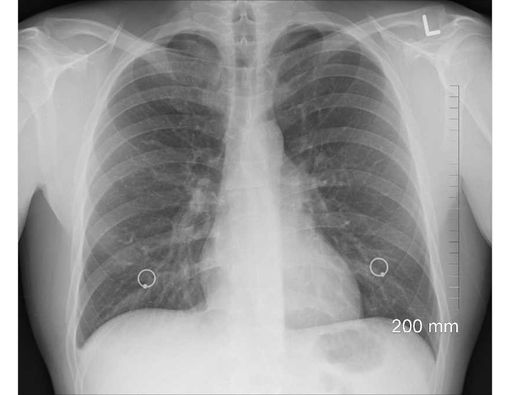

Kerusakan paru akibat tertusuk patahan iga bahkan dapat menyebabkan komplikasi gangguan pernapasan, salah satunya yaitu pneumothorax. Berdasarkan Mayo Clinic, pneumothorax merupakan kondisi ketika udara bocor dan terjebak di rongga pleura, yaitu ruang di antara paru-paru dan dinding dada.

Pneumothorax berbahaya, karena kondisi ini bisa membuat paru-paru mengempis, namun tidak bisa mengembang. Hal ini pada gilirannya menyebabkan paru kolaps.

Ketika paru kolaps, gejala yang bisa muncul tidak hanya sesak napas dan nyeri dada. Penderitanya juga akan mengalami kulit membiru, jantung berdebar, batuk, keringat dingin, serta lemas.